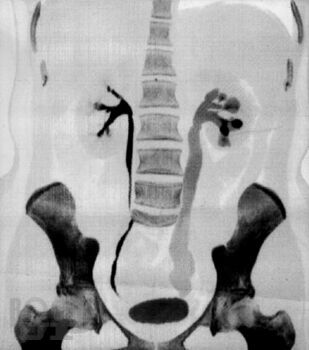

Туберкулез мочеполовой системы

Кратко изложены вопросы этиологии, патогенеза, классификации, диагностики илечения туберкулеза мочеполовой системы. Пособие подготовлено с учетом требований ФГОС ВПО (приказ Минобрнауки РФ от 31.05.2011 г. № 1975), соответствует типовой образовательной программе по специальности 060101 «Лечебное дело», предназначено для студентов 4–5 курсов лечебного факультета и направлено на формирование профессиональных компетенций вих будущей лечебно-диагностической, реабилитационной и профилактической деятельности (ПК 10, 14, 20, 26, 35).